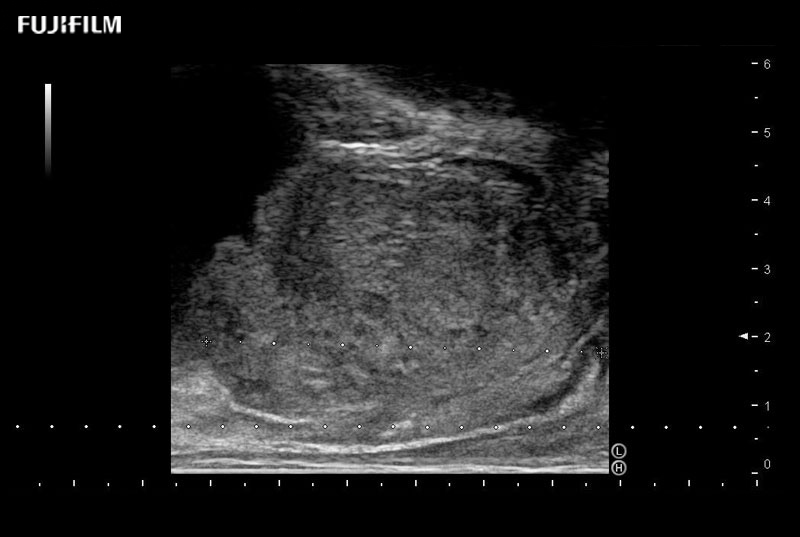

38mm footprint is ideal for scrotal and penile doppler imaging

Larger footprint is ideal for scrotal and penile doppler imaging

Designed for high-resolution imaging of the scrotal and penile regions. This advanced transducer offers exceptional image quality, user-friendly features, and specialized functionalities to support accurate urological diagnostics and enhance patient care.